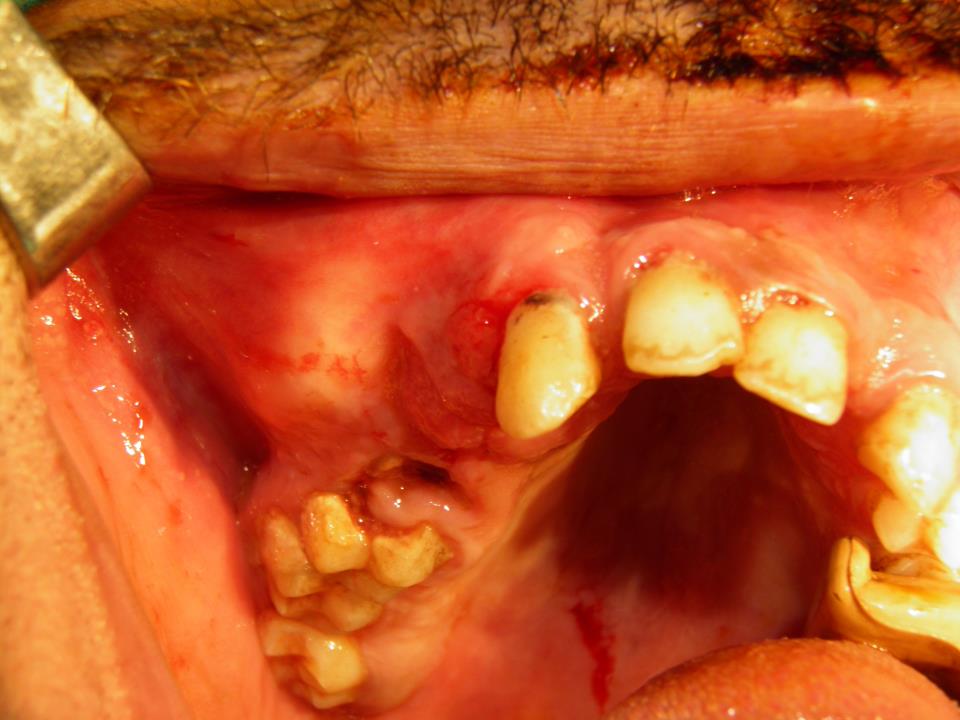

Ameloblastoma Image How Common Is Ameloblastoma It is slow growing and runs a. It's not usually cancerous at first. the most common ameloblastoma is the solid/multicystic/conventional type, making up about 91% of all cases of ameloblastoma. how common is ameloblastoma? They are much more common in the. an ameloblastoma is a rare odontogenic tumor, meaning it originates from the tissues responsible for the. How Common Is Ameloblastoma.

From drgstoothpix.com